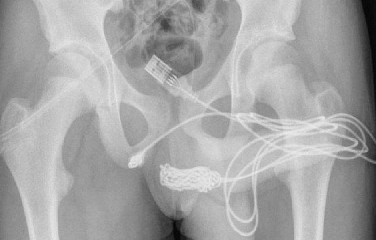

• Adolescente é internado após inserir cabo USB no pênis para tentar medir órgão

4 anos, 3 meses

A régua foi inventada pelo matemático inglês William Oughtred, em 1622. 4 séculos depois, um conterrâneo do pesquisador parece ter esquecido desta invençã...